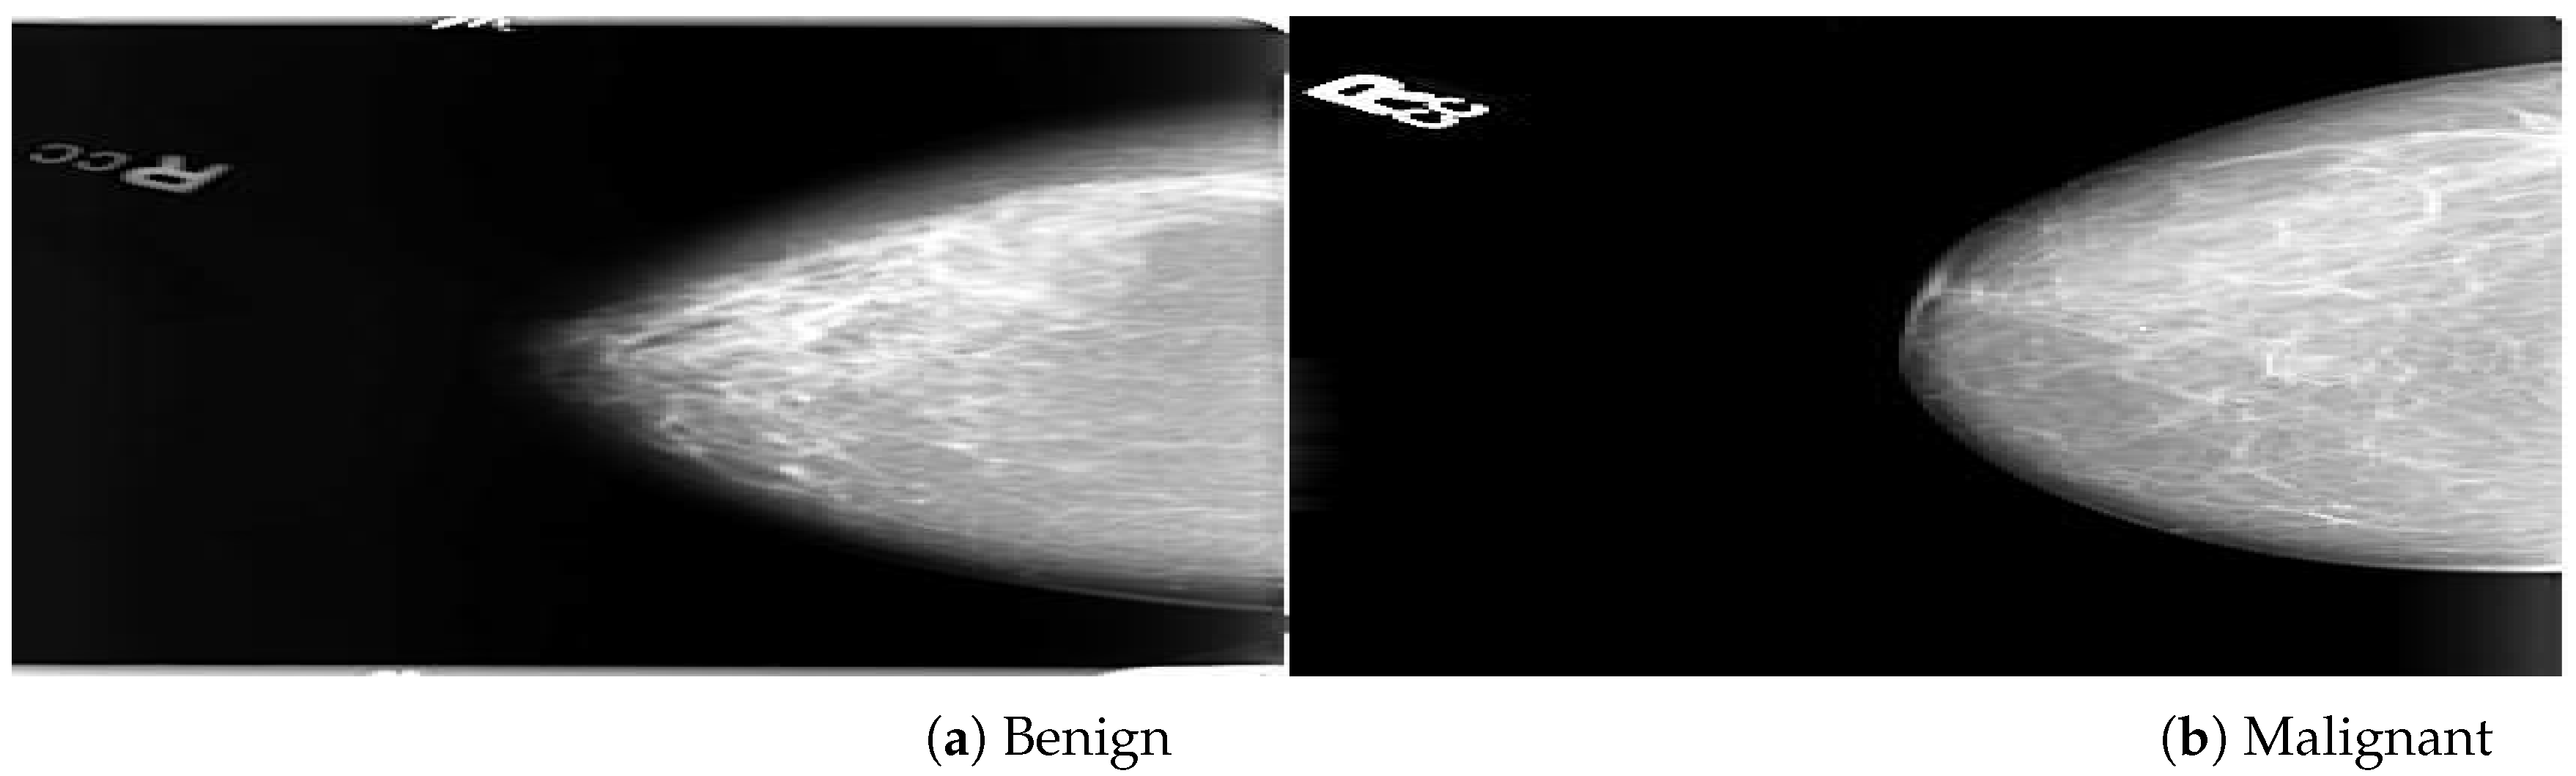

Databases

| Mammogram Label | Category | Images | Dataset |

| Benign (0) | Original | 425 | PINUM |

| Malignant (1) | Original | 152 | PINUM |

| Benign (0) | Augmented | 2550 | PINUM |

| Malignant (1) | Augmented | 912 | PINUM |

| Benign (0) | AD ROIs | 75 | PINUM |

| Malignant (1) | AD ROIs | 75 | PINUM |

| Benign (0) | Original | 1740 | CBIS-DDSM |

| Malignant (1) | Original | 1828 | CBIS-DDSM |

| Benign (0) | AD ROIs | 100 | CBIS-DDSM |

| Malignant (1) | AD ROIs | 100 | CBIS-DDSM |

| Benign (0) | Original | 2500 | DDSM |

| Malignant (1) | Original | 3000 | DDSM |

| Benign (0) | AD ROIs | 100 | DDSM |

| Malignant (1) | AD ROIs | 100 | DDSM |